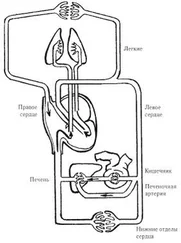

Действительно, язык тесно связан с деятельностью сердца. Царица нашего организма с его помощью выражает свои думы и чаяния. И когда говорят: «Я люблю его (ее) всем сердцем», то это вполне соответствует истине. И наоборот, если ребенок заикается, не может быстро произнести хотя бы пару слов, то это означает, по терминологии китайских целителей, что в меридиане сердца такого пациента поселился «холод» (рис. 32).

Рис. 32. Меридиан сердца (по Г. Лувсан)

1 — цзи-цюань; 2 — цин-лин; 3 — шао-хай; 4 — лин-дао; 5 — тун-ли; 6 — инь-си; 7 — шэнь-мэнь; 8 — шао-фу; 9 — шао-чун

Система инь (+), максимальная активность от 11 до 13 ч, месяц активности — декабрь.

Признаки недостатка энергии: неспособность принимать решения, подавленность, угнетенное состояние, страх, волнение, тревожное состояние. Признаки избытка энергии: те же, что и при недостатке энергии, плюс тяжесть в груди, иногда повышение температуры и сухость во рту.

Показания:боли в области сердца, нарушения сердечного ритма, состояние беспокойства, снижение памяти быстро произнести хотя бы пару слов, то это означает, по терминологии китайских целителей, что в меридиане сердца такого пациента поселился «холод» (рис. 32).